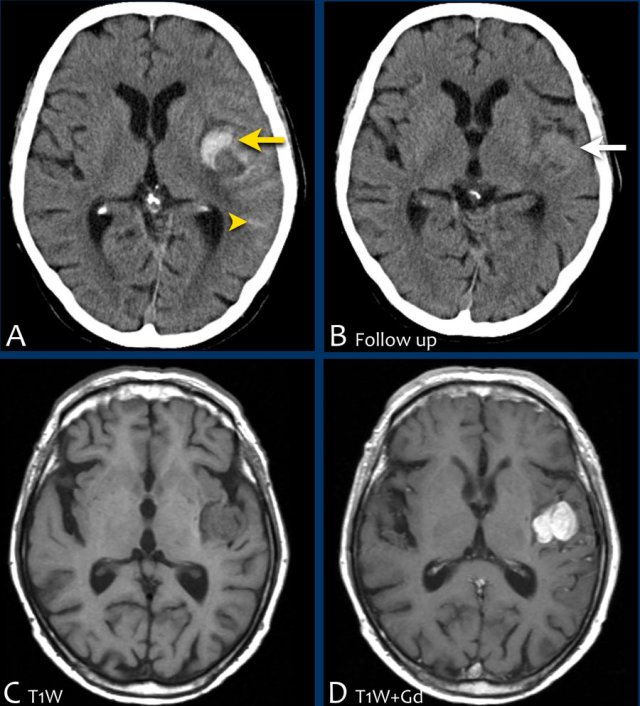

Lobar hemorrhage in Cerebral Amyloid angiopathy (CAA)

This patient with CAA presented with a large lobar hematoma in the right temporal lobe.

Notice the superficial siderosis (arrow).

This patient with CAA has microbleeds, superficial siderosis and multiple infarcts.

Notice the hemorrhage in the pons (yellow arrow).

There is superficial siderosis in the left occipital region.

This patient presented with a cerebellar hematoma.

Continue with the T1W-image...

The T1W-image shows a hyperintense hemorrhage (arrow).